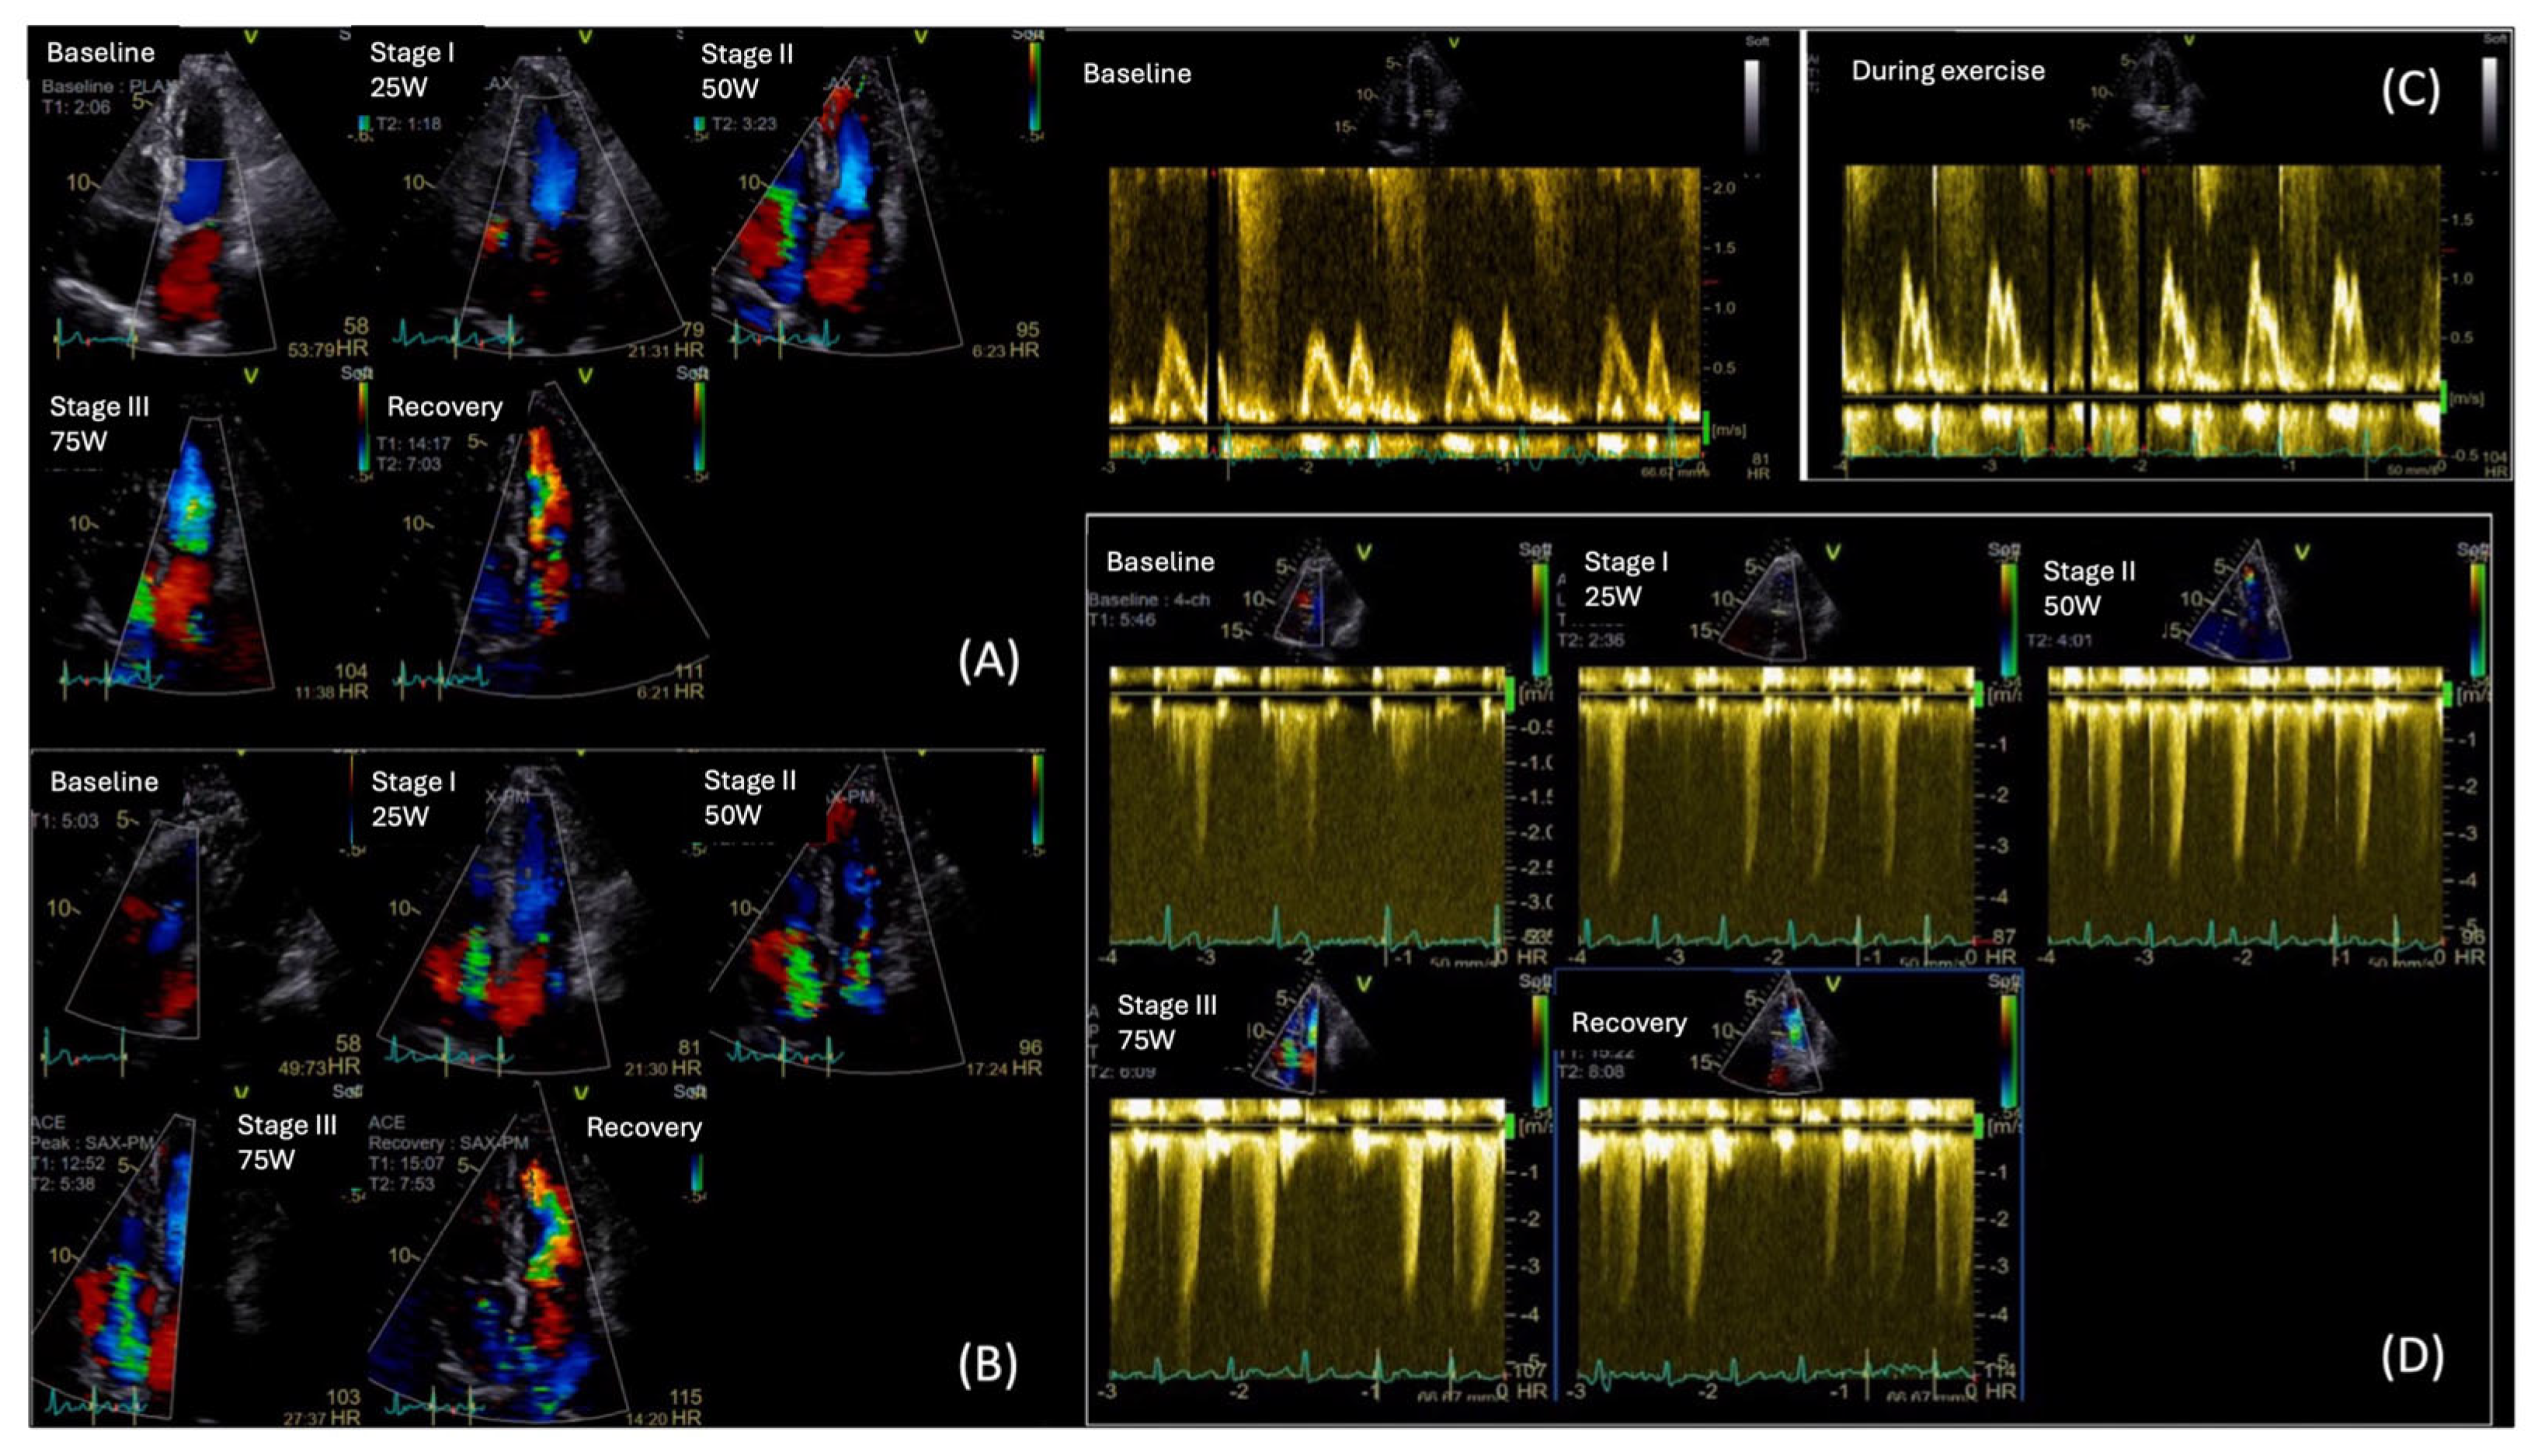

Exercise stress echocardiography (ESE) is a valuable tool for unmasking diastolic dysfunction in patients with unexplained dyspnea and/or fatigue, particularly when the diagnosis remains uncertain due to inconclusive resting echocardiographic findings. The 2020 HFA–PEFF diagnostic algorithm recommends the use of ESE to confirm the diagnosis of HFpEF in cases of intermediate HFA-PEFF score [4,5,86]. The latter score is initially calculated from resting echocardiography parameters and natriuretic peptides levels. The addition of ESE is to reveal exaggerated elevations in LVFP and pulmonary artery systolic pressure (PASP) on exertion.

In clinical practice, ESE is commonly performed using a semi-supine ergocycle protocol with incrementally increasing workload (typically 25-watt increments every 2 min), enabling optimal image acquisition during each exercise stage [88,89,90]. Alternatively, upright bicycle and treadmill protocols are also used, particularly in centers without access to supine ergometry. However, these may limit real-time image acquisition, which can introduce variability due to rapid heart rate recovery [91].

During exercise, a rise in E/E′ and an increase in TR peak velocity (TRVpeak) are often observed in patients with HFpEF, reflecting an abnormal surge in LVFP and PASP, respectively. As heart rate rises, the impaired relaxation in diabetes leads to a disproportionate rise in LVFP and pulmonary pressures, exposing diastolic abnormalities not evident at rest [91,92,93]. Notably, according to the ESC consensus criteria, an exercise E/e′ ≥ 15 and/or TRVpeak > 3.4 m/s are indicative of HFpEF during stress [90]. Moreover, ESE may show an inadequate increase in stroke volume despite rising LVFP, differentiating cardiac limitations from non-cardiac causes of exercise intolerance (Figure 6).

While standard diastolic ESE remains the cornerstone in the evaluation of unexplained dyspnea in patients with suspected HFpEF, recent evidence suggests that a significant subset of symptomatic patients with negative ESE findings may still have HFpEF and a cardiopulmonary exercise test (CPET) could be useful. In a study by Verwerft et al., the use of exercise-induced pulmonary HTN, defined by an elevated mean pulmonary artery pressure to cardiac output slope (mPAP/CO slope > 3 mmHg/L/min), was shown to unmask abnormal cardiopulmonary reserve and impaired pulmonary vascular adaptation in patients with unexplained exertional dyspnea but normal ESE diastolic parameters [94]. Among these patients, elevated mPAP/CO slope strongly correlated with reduced peak VO2 and reduced ventilatory efficiency, supporting its diagnostic and prognostic utility in identifying HFpEF beyond classical criteria [94].

This approach is especially relevant in patients where DBCM may remain undetected by standard evaluation at its early stages. In the study by Gojevic et al., a higher percentage of diabetic patients with exertional dyspnea showed elevated mPAP/CO slopes during exercise compared to asymptomatic diabetic controls; however, the difference between groups was not statistically significant. This underscores the complexity of interpretation and highlights the need for further research to define the diagnostic and prognostic role of mPAP/CO slope in diabetic cardiomyopathy [95]. From the practical point of view, the combination of echocardiography and CPET has the potential for higher accuracy than ESE per se.

Beyond diastolic assessment, ESE evaluates contractile reserve, often impaired in the early stages of DBCM, even when the resting LVEF > 50%. A failure of exercise to increase LVEF or stroke volume may be an early sign of HFpEF [96]. In the diabetic population, GLS is often mildly reduced at rest and fails to augment appropriately during stress, indicating impaired systolic reserve [97]. Likewise, a blunted rise in peak systolic strain rate (SRs) during ESE reflects reduced contractile reserve, making these strain-based measures valuable for early diagnosis of subclinical DBCM [97].

MW provides an assessment of LV function and GLS by incorporating afterload assessment via the blood pressure measurement [98]. While MW has proven effective in identifying early, subtle abnormalities in HFpEF patients at rest, only a limited number of studies have investigated how these parameters respond to physiological stress. A dynamic evaluation may reveal impairment in these indices during stress that is masked at rest [98,99]. In the study of Zhang et al. (2025), which enrolled 40 patients with HFpEF and 40 normotensive controls, the HFpEF group demonstrated significantly lower increases in GWI and GCW, along with significantly greater increases in GWW and a more pronounced decline in GWE from rest to peak exercise compared to controls; these changes in MWI were closely associated with reduced exercise tolerance [100]. Inherent drawbacks of STE analysis in higher heart rates with reduced frame rates limit their clinical applicability [101].